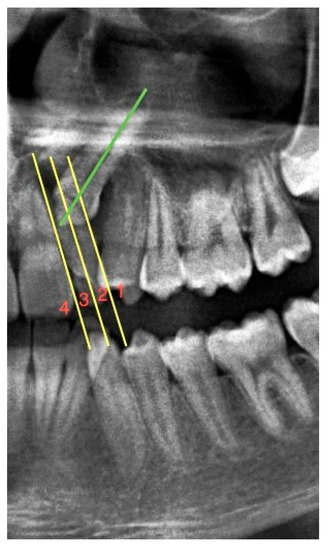

In determining the mesiodistal angular positions of impacted maxillary canines, the bicondylar plane drawn from the uppermost and anterior points of the right and left condyles was created as a fixed reference [22]. The medial angle between this reference line and the long axis of the canine was measured and recorded (see Figure 2).

Figure 2.

A panoramic radiograph showing the angle between the right and left impacted maxillary canines and the bicondylar plane, separately. B: Bicondylar plane, the junction of the uppermost and anterior points of the condyles; La: line passing through the long axis of the canines; O: occlusal plane; x: perpendicular distance of the cusp apex of the canine from the occlusal plane; and α: medial angle between the long axis of the canine and the bicondylar plane.

On panoramic radiographs, the distance of the impacted maxillary canines to the occlusal plane was recorded by measuring the distance of the vertical line descending from the canine cusp apex to the occlusal plane [23] drawn between the maxillary central incisor and the mesial tubercle of the maxillary permanent first molar (see Figure 2).